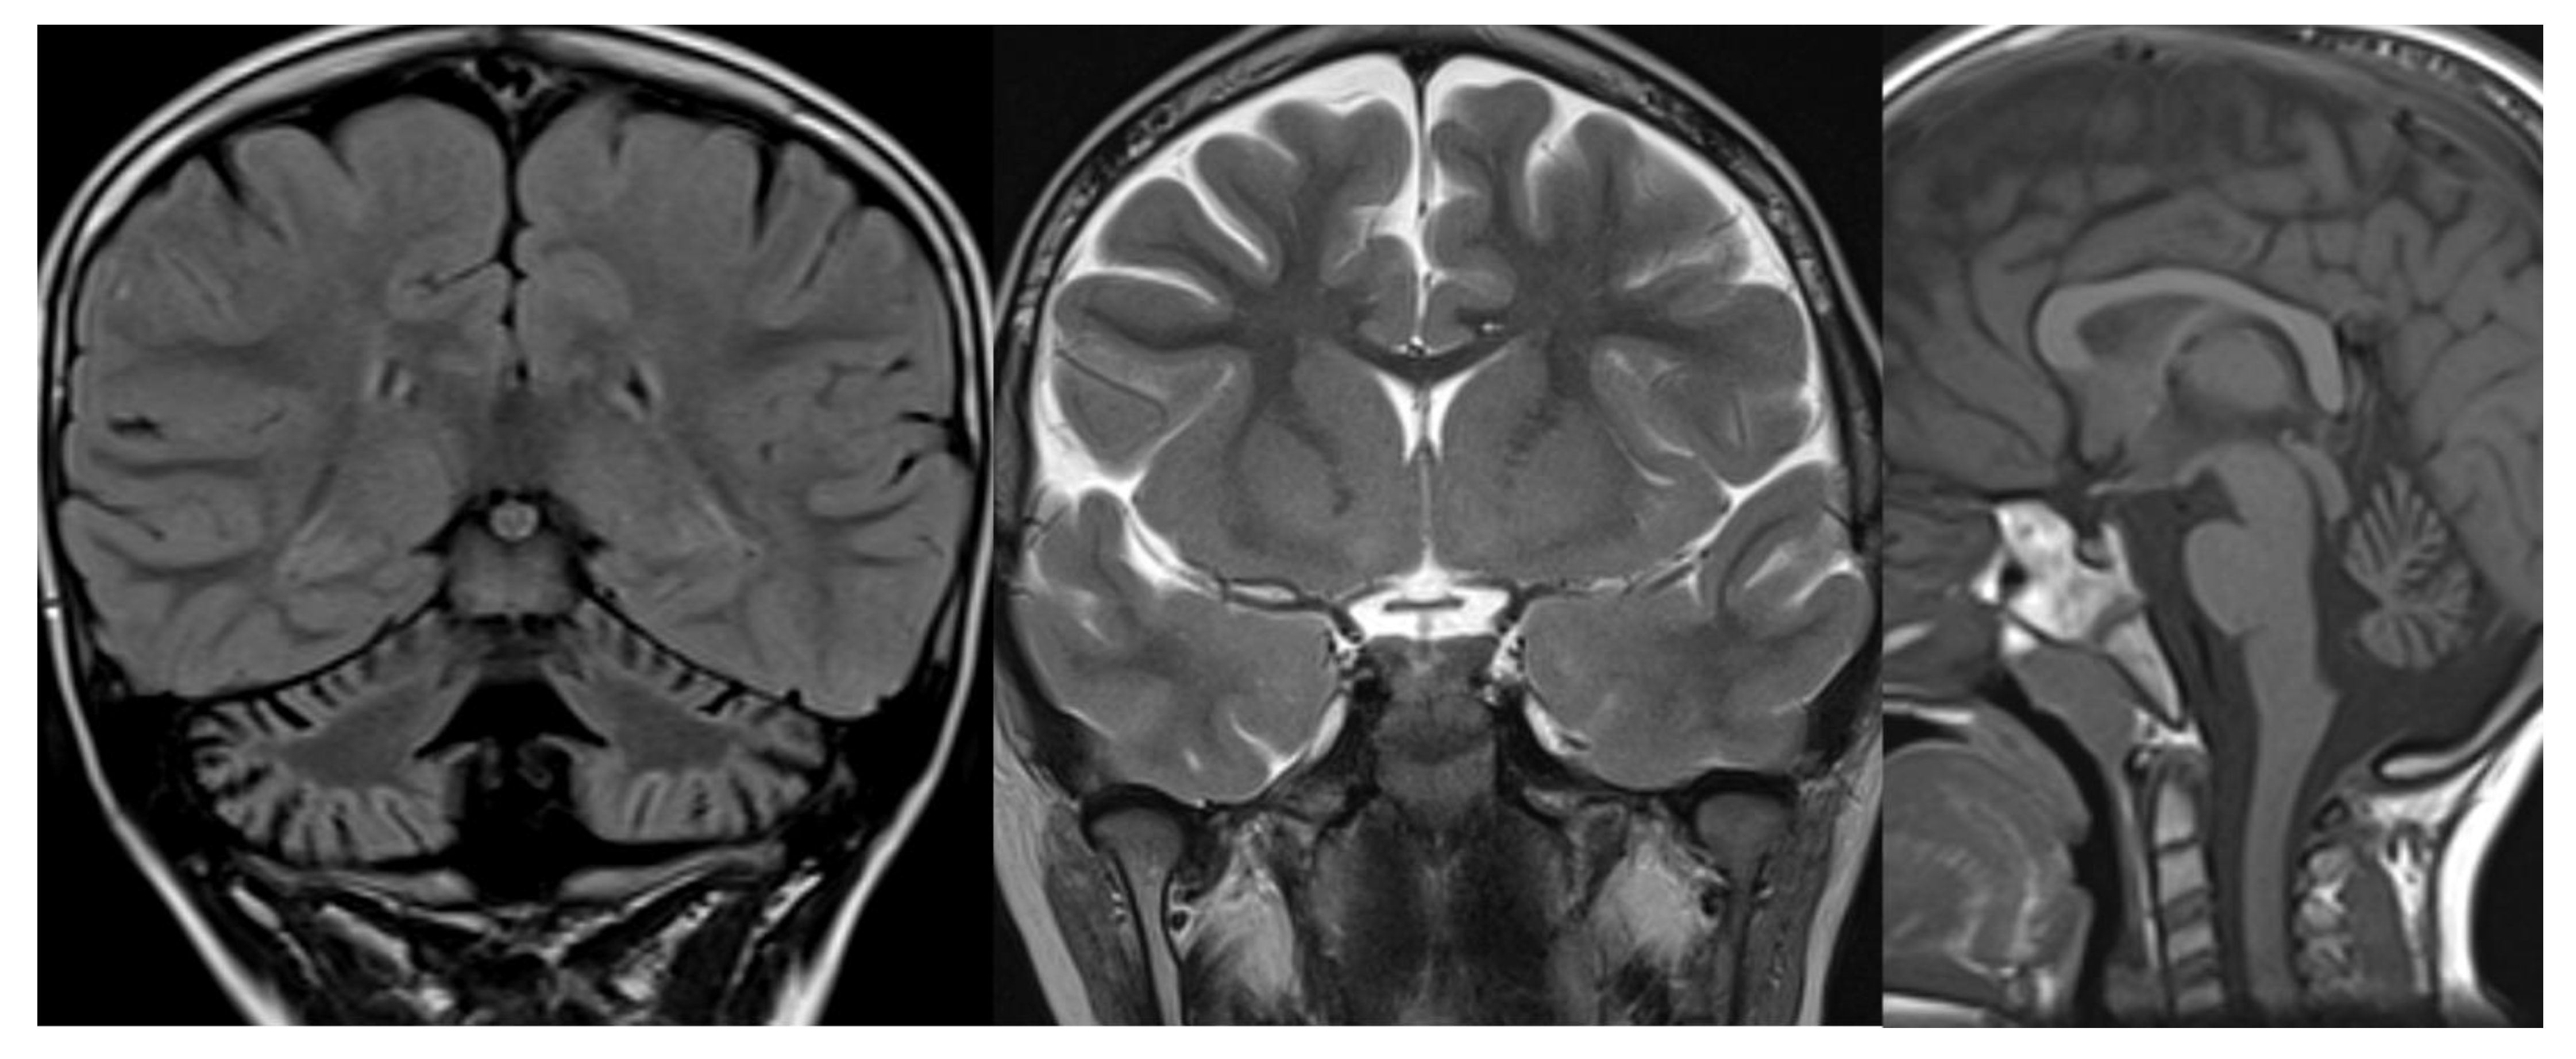

Most children with CDG1A have small pontine protuberance, shrunken appearance of the superior vermis and flattened inferior vermis, and hyperintense hemispheric cerebellar cortex at birth. In milder cases, the initial radiological findings could be normal with a subsequent atrophic evolution (Figure 5).

Figure 5.

GDC1a. Brain MRI scan of a boy. At 10 years (top), the exam demonstrates only slight cerebellar atrophy and hyperintensity in the dentate nuclei. The exam at 12 years (bottom) shows a severe worsening of cerebellar atrophy with the persistence of normal brainstem volume.

The cerebellar white matter is also slightly hyperintense compared with supratentorial white matter, leading to the typical “bright cerebellum” appearance. 1H-MRS shows a markedly reduced NAA peak [22]. Pathological findings suggest very early-onset hypoplasia followed by progressive atrophy [22,23].

Radiological imaging is limited to MRI since CT and studies with x-rays can increase the risk of genetic mutation in these patients highly sensitive to DNA damage by ionizing radiation [37,38]. MR images reveal diffuse cerebellar atrophy, with initial involvement of the superior vermis and lateral cerebellar hemispheres and unusual decreased cortical thickness along cerebellar hemispheres. Supratentorial brain shows no sign of volume loss. At the same time, confluent hyperintensities in T2/FLAIR and multiple focal hypointensities (thought to be deposits of haemosiderin related to capillary telangiectasia) are seen in deep white matter, mainly in adult patients [39]. Hypoplasia of the inferior vermis and a large cisterna magna were also frequent signs [40] (Figure 7).

Figure 7.

Ataxia telangiectasia (AT). Brain MRI scan of a 10-year-old girl. MR images reveal severe atrophy of the cerebellar hemispheres, decreased thickness of the cortex of superior cerebellar hemispheres, and hypoplasia of inferior vermis.